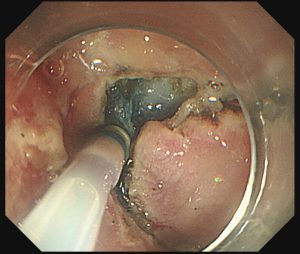

内視鏡的粘膜下層切開剥離術:ESD は、特殊なナイフを使ってEMRでは切除が困難な部位やサイズの大きな腫瘍などを切除する方法です。

ナイフを用いて切り取るため

理論的に切除する組織の大きさに制限がなく、広い病変を一度に

剥離することができます。